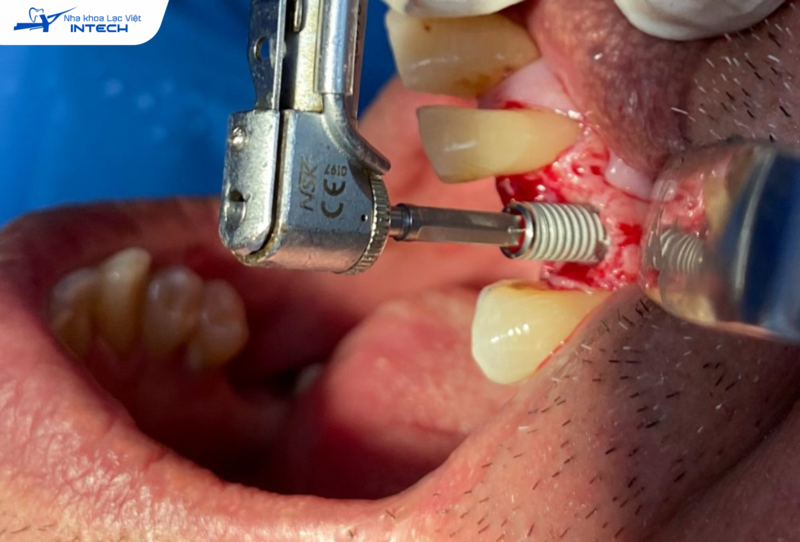

• Làm sạch răng của khách hàng bằng dụng cụ siêu âm để loại bỏ mảng bám/cao răng tích tụ trên bề mặt Implant và vùng nướu xung quanh, giúp làm sạch triệt để khu vực viêm nhiễm, giảm nguy cơ lây lan.

• Nạo vét các tổ chức viêm quanh chân răng Implant để loại bỏ hoàn toàn tác nhân gây viêm, đồng thời tái lập lại khả năng bám dính của nướu quanh Implant, giúp bảo vệ trụ Implant và mô mềm xung quanh.

• Nếu viêm nhiễm đã gây tổn thương nghiêm trọng, bác sĩ có thể thực hiện phẫu thuật để loại bỏ mô viêm, nạo vét túi nha chu, hoặc nâng nướu, ngăn chặn tình trạng viêm tiếp diễn.